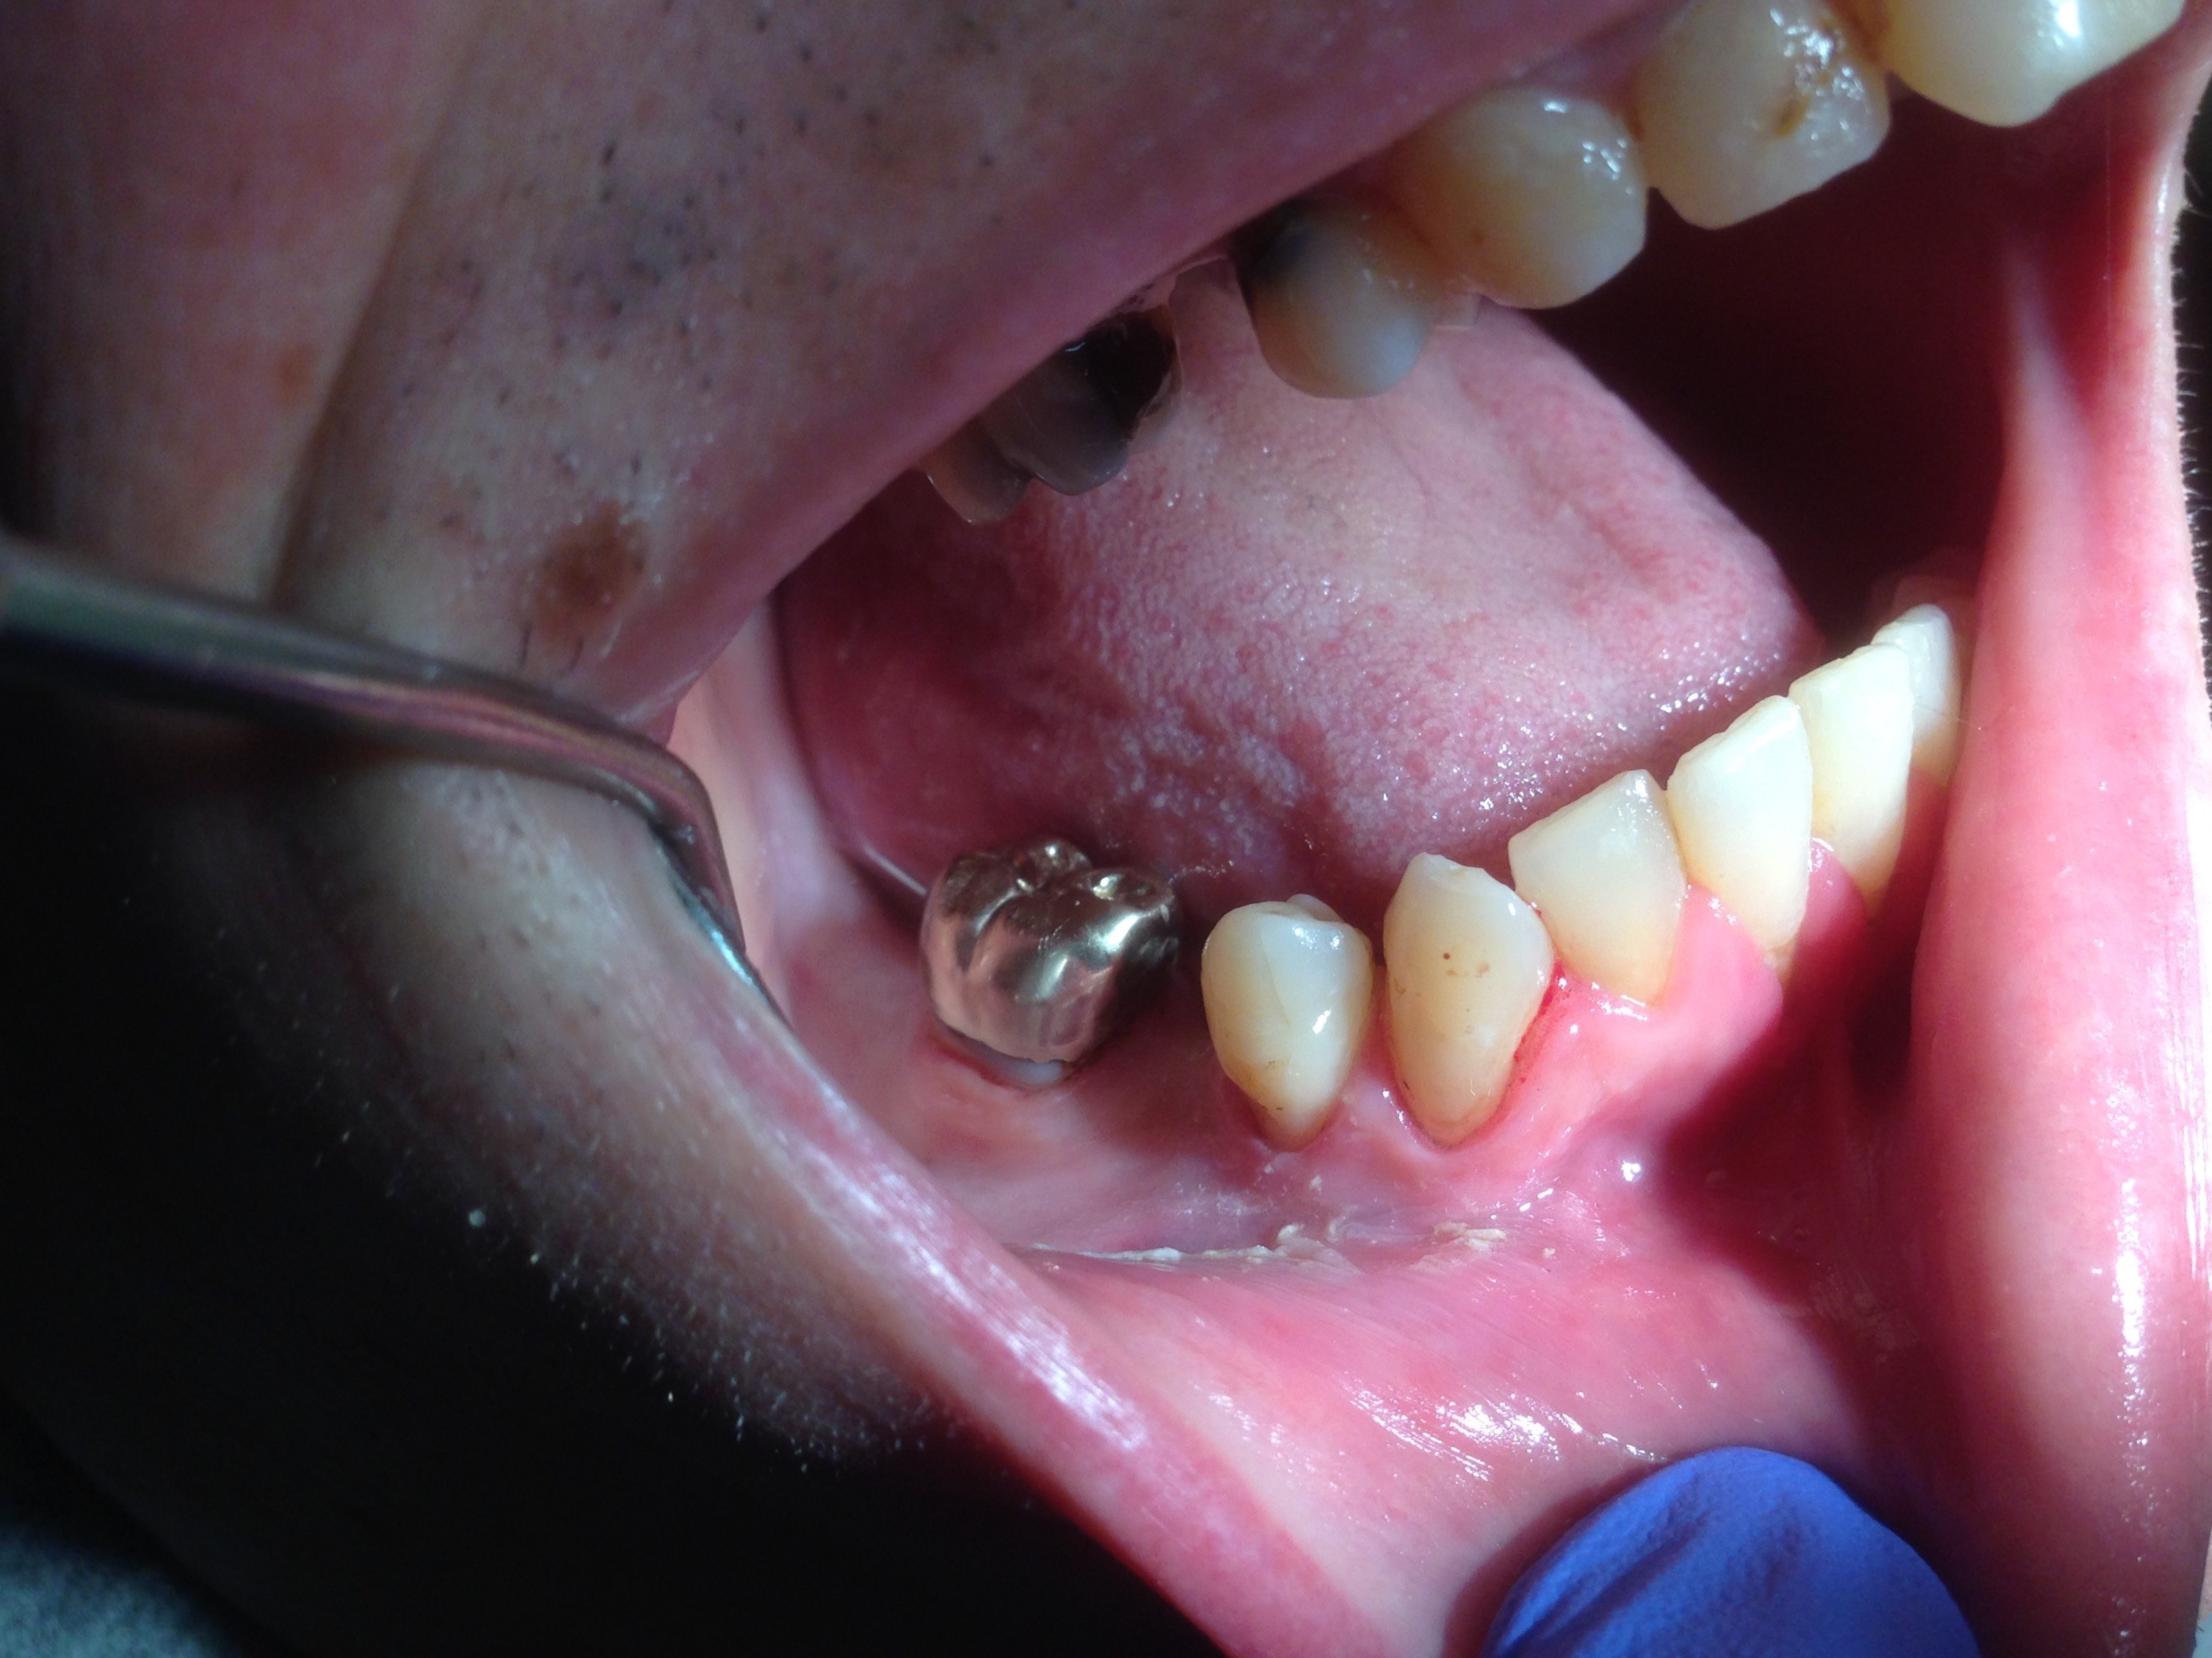

The patient shown in Figure 4 through Figure 6 was a meth user for 6 years. He had a stroke at age 22. After recovering from the stroke and stabilization of his circulatory system was achieved, and once he quit using meth, he strongly desired to apply for a job and wished to improve his dental appearance. He opted to have all of his teeth extracted, as complete dentures were his only treatment option because there were no adequate abutment teeth remaining for placement of removable partial dentures.

Fig 4 through Fig 6. Patient’s oral condition after 6 years of meth use.

Figure 5

Figure 6